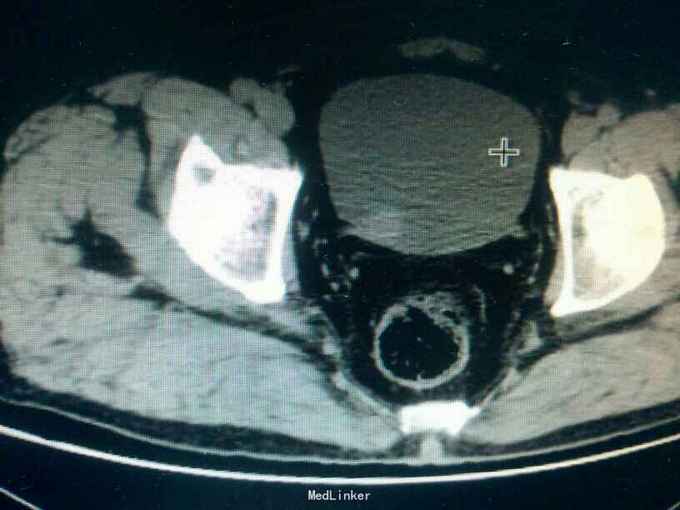

主诉:反复肉眼血尿3年。 病史:入院3年前,无明显诱因偶然发现小便呈淡红色,无明显尿频,尿急,尿痛,腰部疼痛发热等症状,后血尿广症状自行消失。一周前小便呈红色,为进一步检一治疗,来院检查。

专科查体无特殊。 ct检查结果提示,膀胱壁查见多个稍强回声闭,最大约3*3cm

诊断:膀胱癌。 治疗:膀胱肿瘤电切术,术后使用吡柔比星膀胱灌注。